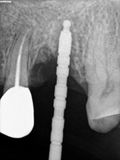

fredlibc | all galleries >> Galleries >> RYang - immediate 26 and apico 25 > R2.jpg